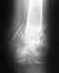

Компрессионый перелом L2

Остеохондроз L1-2, L2-3,L3-4, L4-5,L5-S1 - III степени.Задняя срединная протрузия диска L3-4 с диско-дуральной компрессией - II степени. Диффузное выпячивание дисков L 1-2, L 2-3, L4-5,L5-S1. Застарелый, компрессионный, сгибательный, стабильный перелом тела L2. Описание:На серии КТ-грамм поясничного отдела позвоночника в аксиальной проекции поясничный лордоз выражен. Имеется застарелый, сгибательный, стабильный перелом тела L2 позвонка II степени. Дегенеративные изменения в дисках L1-2,L2-3,L3-4,L4-5,L5-S1.Высота дисков снижена. Диффузное выпячивание дисков L1-2,L2-3,L4-5,L5-S1 до 4мм в передне-заднем направлении, с диско-дуральной компрессией I степени.Задняя серединная протрузия диска L3-4, 14*6,5мм с диско-дуральной компрессией II степени. Передне-задний размер позвоночного канала на уровне L4 = 16мм. Окружающие ткани без особенностей.Повторюсь, что моей маме 65 лет, последние 15 из которых она ведёт малоподвижный образ жизни(Инвалид I группы Болезнь Паркинсона)Когда у неё месяц назад начались боли в пояснице врач порекомендовал ей пить обезболивающие препараты и всё. Поэтому КТ мы делали по собственной инициативе (Направление просто вымолили у участкового терапевта)И что нам теперь делать с результатами,к какому специалисту обращаться мы понятия не имеем. Подскажите пожалуйста куда обращаться, насколько страшен диагноз и сможет ли мама в своём состоянии(приступы паркинсонизма)вылечиться. Заранее спасибо за ответ.Дай Вам Бог здоровья.